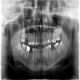

Diagnostyka radiologiczna jest jednym z podstawowych badań poprzedzającym właściwe leczenie pacjentów stomatologicznych. Zdjęcia RTG które wykonujemy w naszych gabinetach, pozwalają ocenić stan zęba, korzeni, tkanek, a także kości. Dokładne rozpoznanie może ułatwiać ułożenie indywidualnego planu leczenia i tym samym zwiększać szanse na skuteczną terapię. Pacjentom odwiedzającym nasze gabinety stomatologiczne proponujemy wykonanie zdjęcia zębów dla ortodonty, do leczenia kanałowego oraz pantograficzne, ukazujące żuchwę, stawy skroniowo-żuchwowe, a także zatoki szczękowe.

Nasza pracownia radiologiczna wyposażona jest w aparaty nowej generacji, dzięki którym możliwe jest wykonanie szerokiej diagnostyki. Wykonane przez nas zdjęcia RTG, w tym pantograficzne, mogą posłużyć nie tylko w leczeniu ortodontycznym, ale również w endodoncji i implantologii. Badanie rentgenowskie jest nieiwazyjne, nie zajmuje wiele czasu, a my dokładamy starań, aby pacjenci możliwie jak najszybciej otrzymywali wywołane zdjęcia uzębienia.

Jak wspomnieliśmy, obrazowa diagnostyka jest niezbędna m.in. podczas wizyty u ortodonty. Lekarza w takim przypadku interesuje rozkład zębów, stan korzeni czy przyzębia. Wszystkie niezbędne informacje do rozpoczęcia leczenia daje właśnie obrazowanie rentgenowskie. Może się okazać, że konieczna będzie jeszcze dokładniejsza diagnostyka – wówczas w naszym gabinecie można wykonać zdjęcie pantograficzne. Ten rodzaj badania uwidoczni np. zawiązki zębów.